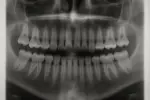

영국 노팅엄대학교 연구진과 국제 공동연구팀은

손상된 치아 법랑질을 재생하고, 건강한 법랑질을 강화하며, 충치 위험을 예방할 수 있는 단백질 기반 생체모사 젤

을 개발했다.